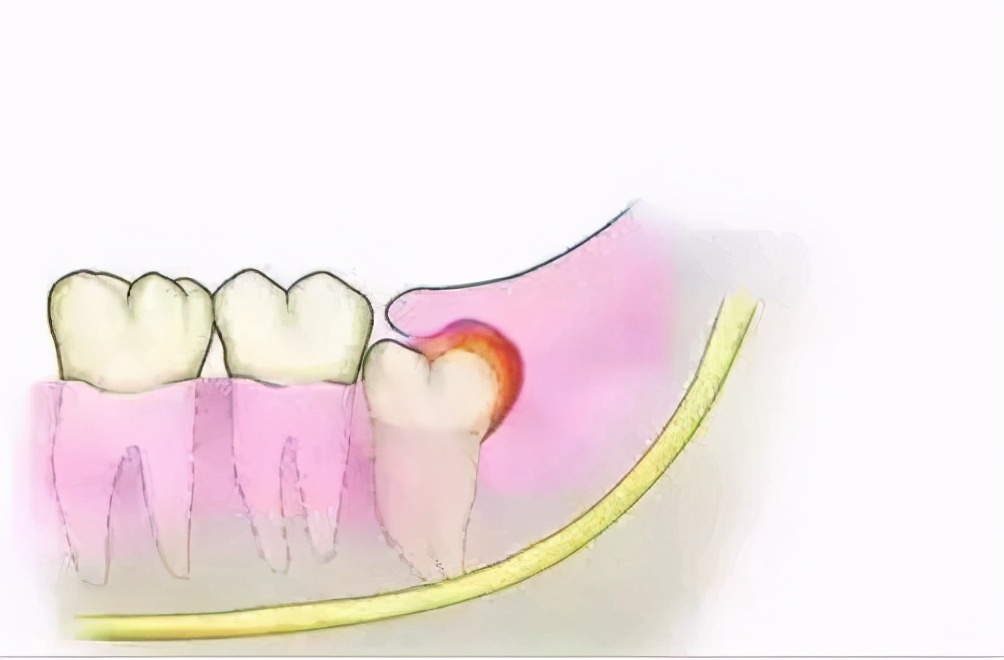

4.冠心炎引起的牙痛

这是由冠周围的软策划的感染和炎症引起的。刚开始时,牙龈肿痛。病人在说话,喝水和进食时都会感到疼痛。在严重的情况下,他不会说话,只能咬紧牙关才能缓解。您可以尝试人工牛黄甲硝唑胶囊。如果不能有效治疗该病,它将发展成慢性病并复发!